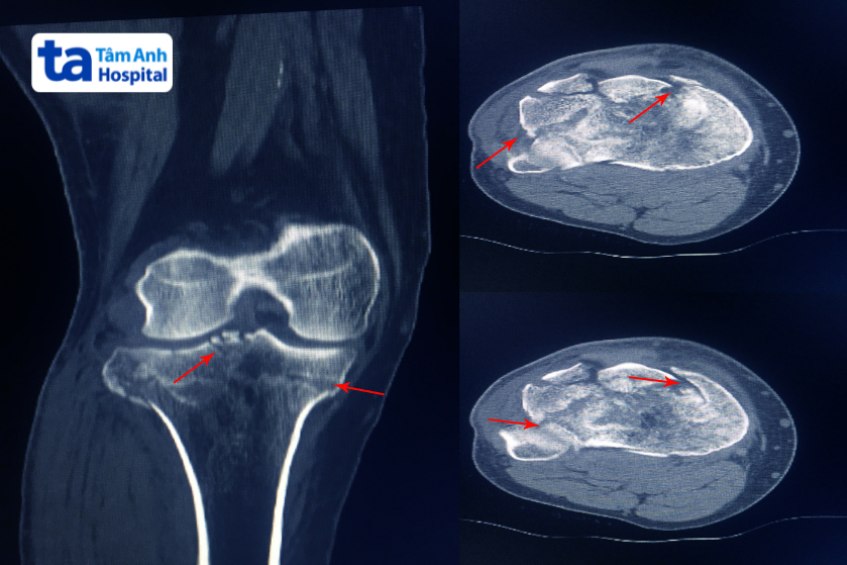

Dưới đây là một số hình ảnh vỡ xương mâm chày: